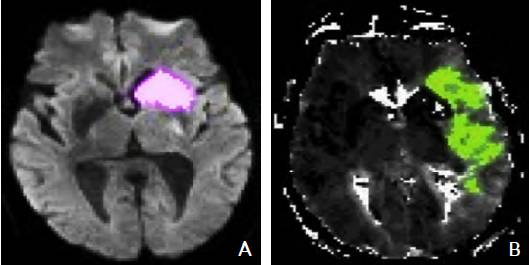

5.2.3 磁共振成像DWI-PWI不匹配区

MRI PWI常采用动态磁敏感对比增强技术,通过对比剂团注追踪技术进行动态增强扫描,依靠对比剂磁化率改变引起信号变化的原理成像。经处理后可得出相应灌注成像的参数如CBF、CBV、MTT及TTP等。研究表明,CBF下降和MTT延长是组织缺血的相对敏感指标,但存在过分估计最终梗死体积的可能性;TTP图像上脑灰质、白质之间无明显区别,可以清楚显示病变的范围和边界。虽然目前识别缺血半暗带的方法有多种,但MRI DWI与PWI不匹配区是急诊过程中判断缺血半暗带较切合实际的方法(图4)。一项回顾性研究认为,PWI的病灶面积是DWI病灶面积的2.6倍时早期再灌注的治疗效果最好。

图4 磁共振成像DWI-PWI不匹配区影像 注:A:磁共振DWI序列:高信号的梗死区(粉色标记区);B:磁共振PWI序列:梗死区周围的缺血半暗带(绿色标记区)。DWI:弥散加权成像;PWI:灌注加权成像